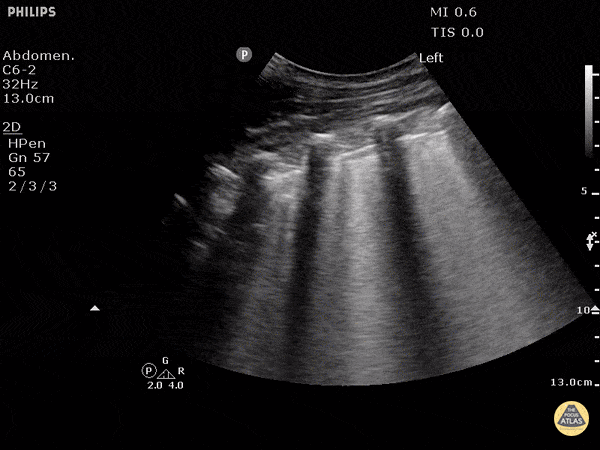

B-lines obtained with curved probe. B-lines are vertical artifacts that move with respiration from the pleural surface. They represent increased water in an area of the lung. In the right clinical context this could represent pulmonary edema. An increase in B-lines correlates with the degree of pulmonary edema. 3 B-lines in an intercostal space represent a "positive" region of the lung, and if there are two regions of the lung that are positive, you can diagnose pulmonary edema. Dr. Justin Bowra et al. (Dr. D Browne and Dr. J Knights)